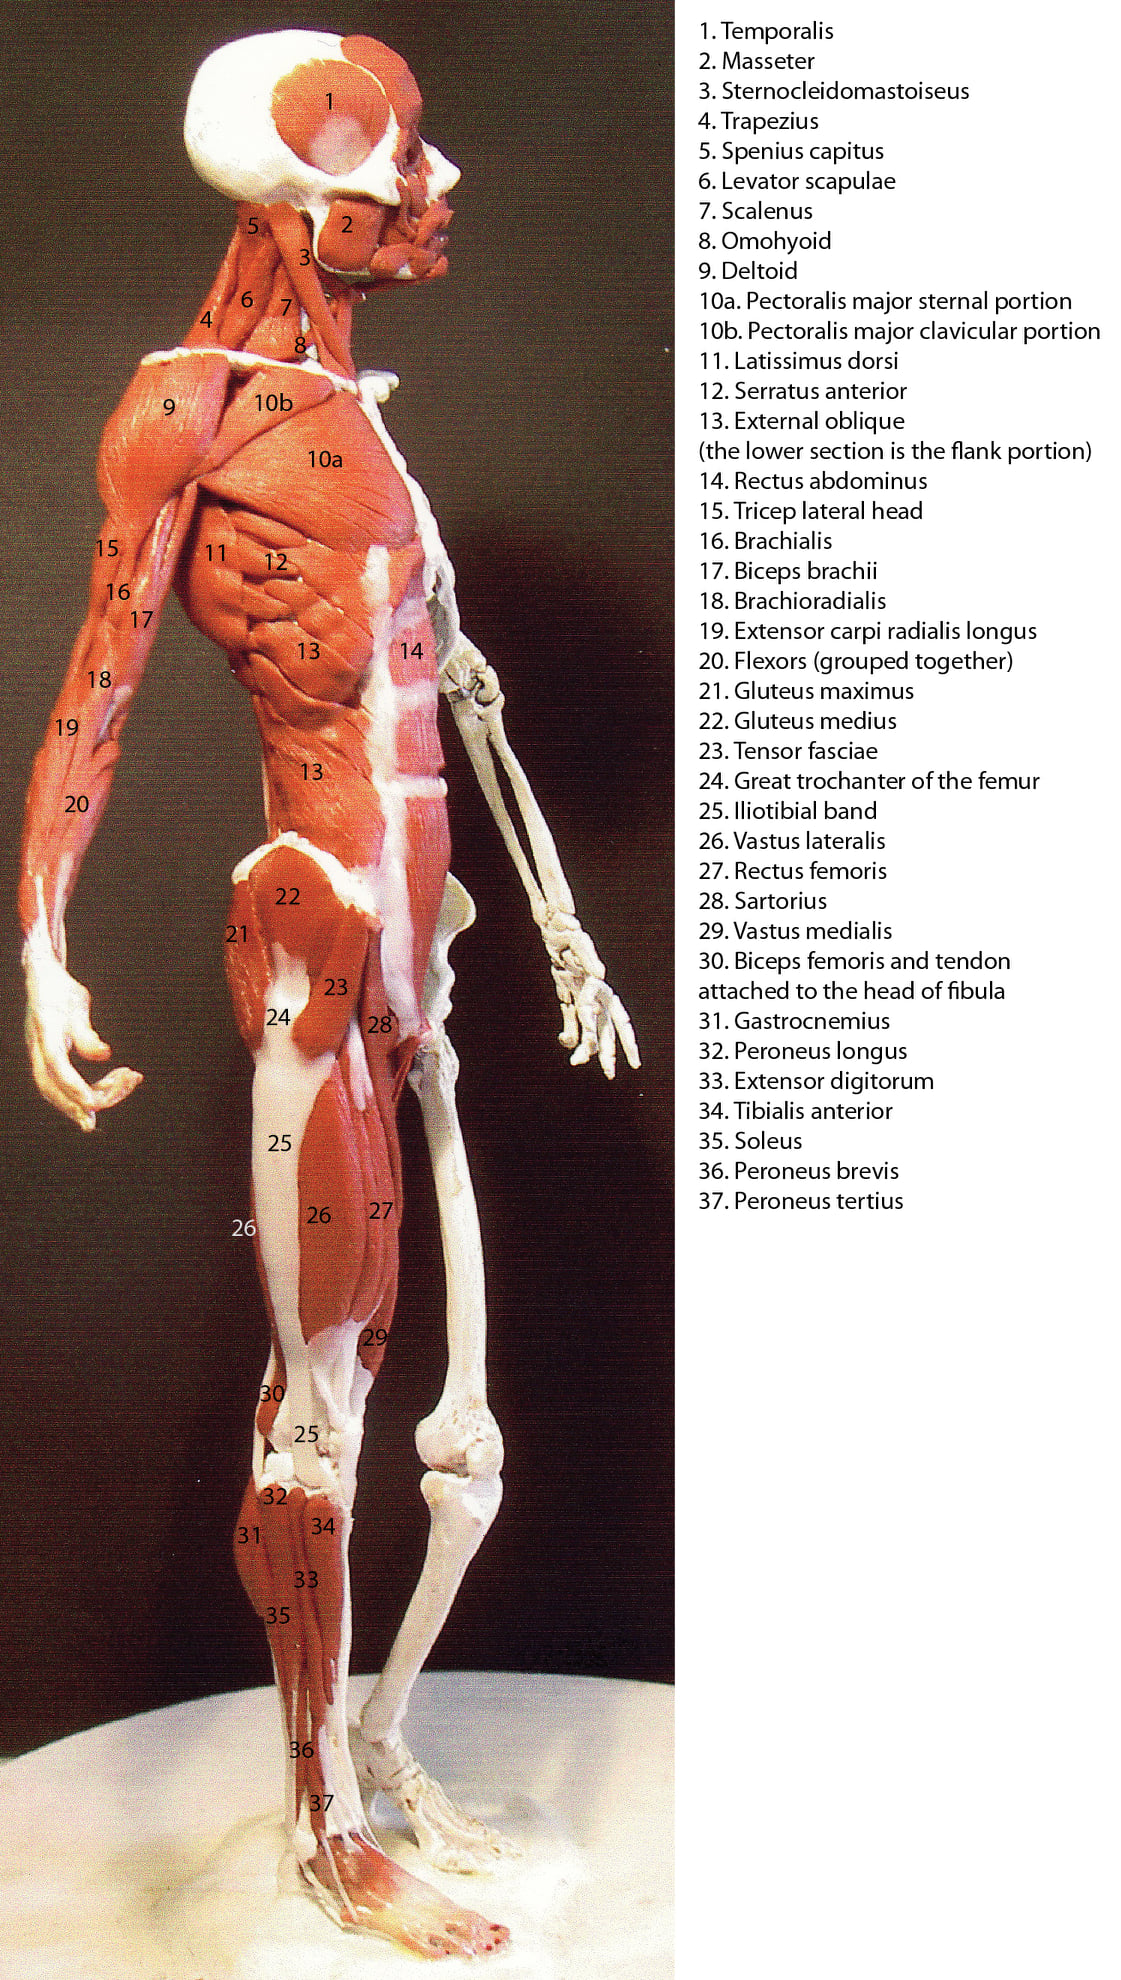

Ecorche' (ekorshay) Fr. Anatomical figure of an animal or human with the skin removed to show the location and interplay of the muscles.

This method of the ages old study of human anatomy through sculpture process was created by Rey Bustos. His students are required to construct their own ecorche as an indepth, hands on, 3D study of human anatomy, an exciting prospect for any student of medical science, whether at online colleges or doing their fellowship. These models are constructed in 1/4 scale from clay with a wire armature. The left arm bends at the elbow!

Ecorche' (ekorshay) Fr. Anatomical figure of an animal or human with the skin removed to show the location and interplay of the muscles This method of the ages old study of human anatomy through sculpture process was created by Rey Bustos. His students are